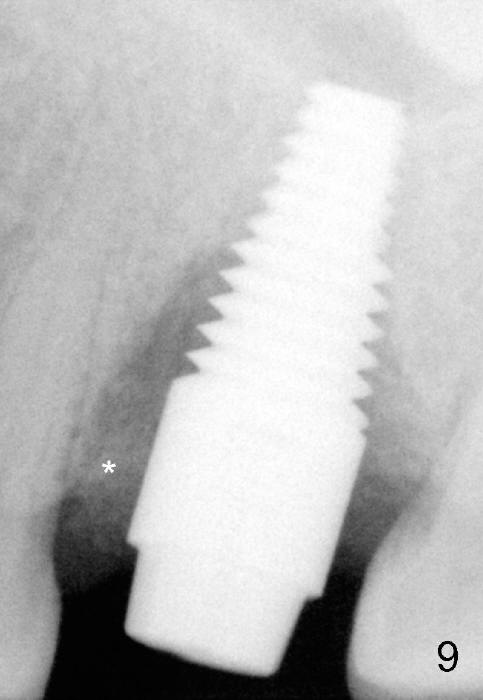

Bone density around the molars (including apical to #14) (Fig.1 black *) is higher than that around the premolar (white *). In fact the tooth has horizontal root fracture (Fig.2: <: CEJ), consistent with high bone density (strong mastication). An immediate implant is planned (Fig.3). After extraction, osteotomy starts at the buccal slope of the palatal (Fig.4 P) socket. Because of high bone density apical to the sockets, drills are required for osteotomy in the septum (type II bone) instead of osteotomes and primary stability is easily achievable (>60 Ncm). When a 7 mm implant (Fig.6 I)) is placed, the peri-implant gaps are much smaller (*) than that with a 4.5 mm tap (Fig.5 T). This helps bone grow faster toward implant. A long implant (17 mm) is necessary for this case to obtain primary stability in the apical one (double arrows in Fig.6). With reamers, a fair amount of autogenous bone is harvested during drilling, mixed with allograft and synthetic bone and placed in the remaining buccal (Fig.7) and palatal (Fig.8) sockets. The openings of the buccal and palatal sockets are covered with collagen dressing (C) and perio dressing. The latter is kept in place by a short abutment (Fig.6-8 A).